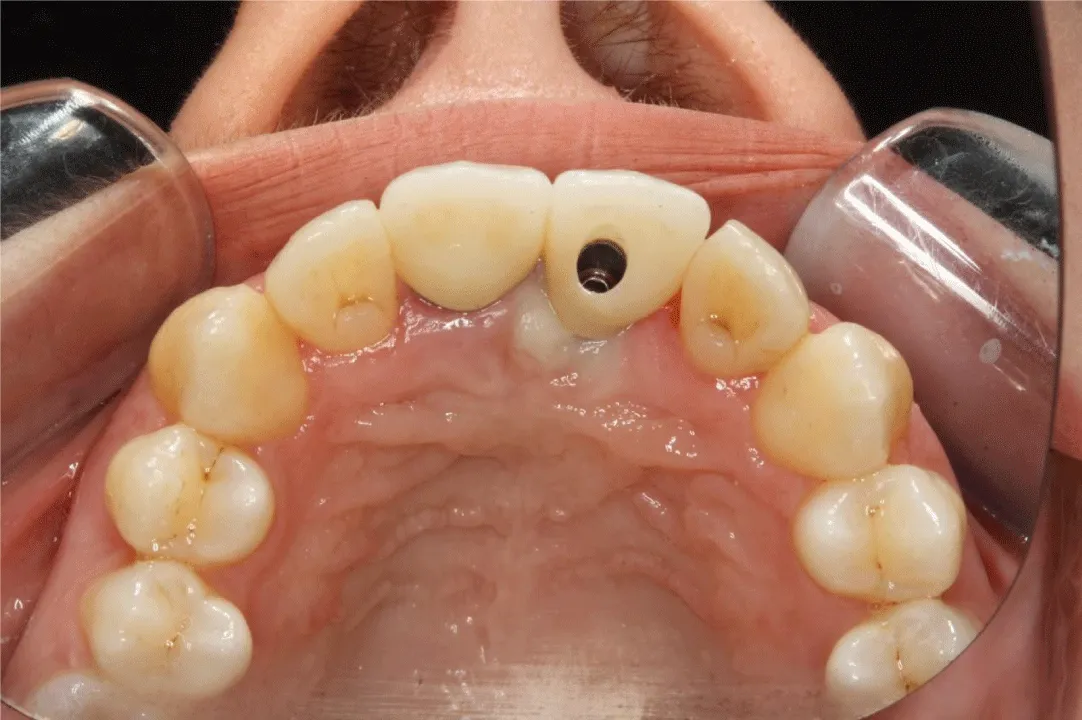

Two weeks later, a titanium dental implant (Brånemark System Mk III RP 3.75×18mm, Nobel Biocare, Gothenburg, Sweden) was placed in the position of the missing left central incisor (Figure 3). The implant achieved bicortical anchorage with adequate primary stability.

Final superstructures were then created (Figure 4). Try-in of the maxillary right central incisor’s all-ceramic crown and the metal framework of the left central incisor’s implant screw-retained metal-ceramic crown (FPD) was performed, in order to be sure about their passive fit and the occlusal alignment, and esthetics were verified prior to crown processing, by using table salt to minimize gag-reflex. An occlusal registration was performed using PVS material. The patient again played the instrument in the clinic to confirm the contour, before the final prostheses were screwed and cemented, accordingly (Figure 5).

The all-ceramic crown was fitted and cemented with a dual-cure resin cement and the implant metal-ceramic crown was screwed. Try-in was performed, and occlusion and esthetics were verified. The crowns were fitted, cemented, and screwed with a (final) torque of 25N/cm2, accordingly. The crowns’ design resulted in esthetics and comfort and the menopausal clarinetist was instructed in prostheses’ hygiene. A schedule of periodic maintenance appointments was set to re-evaluate patient compliance.